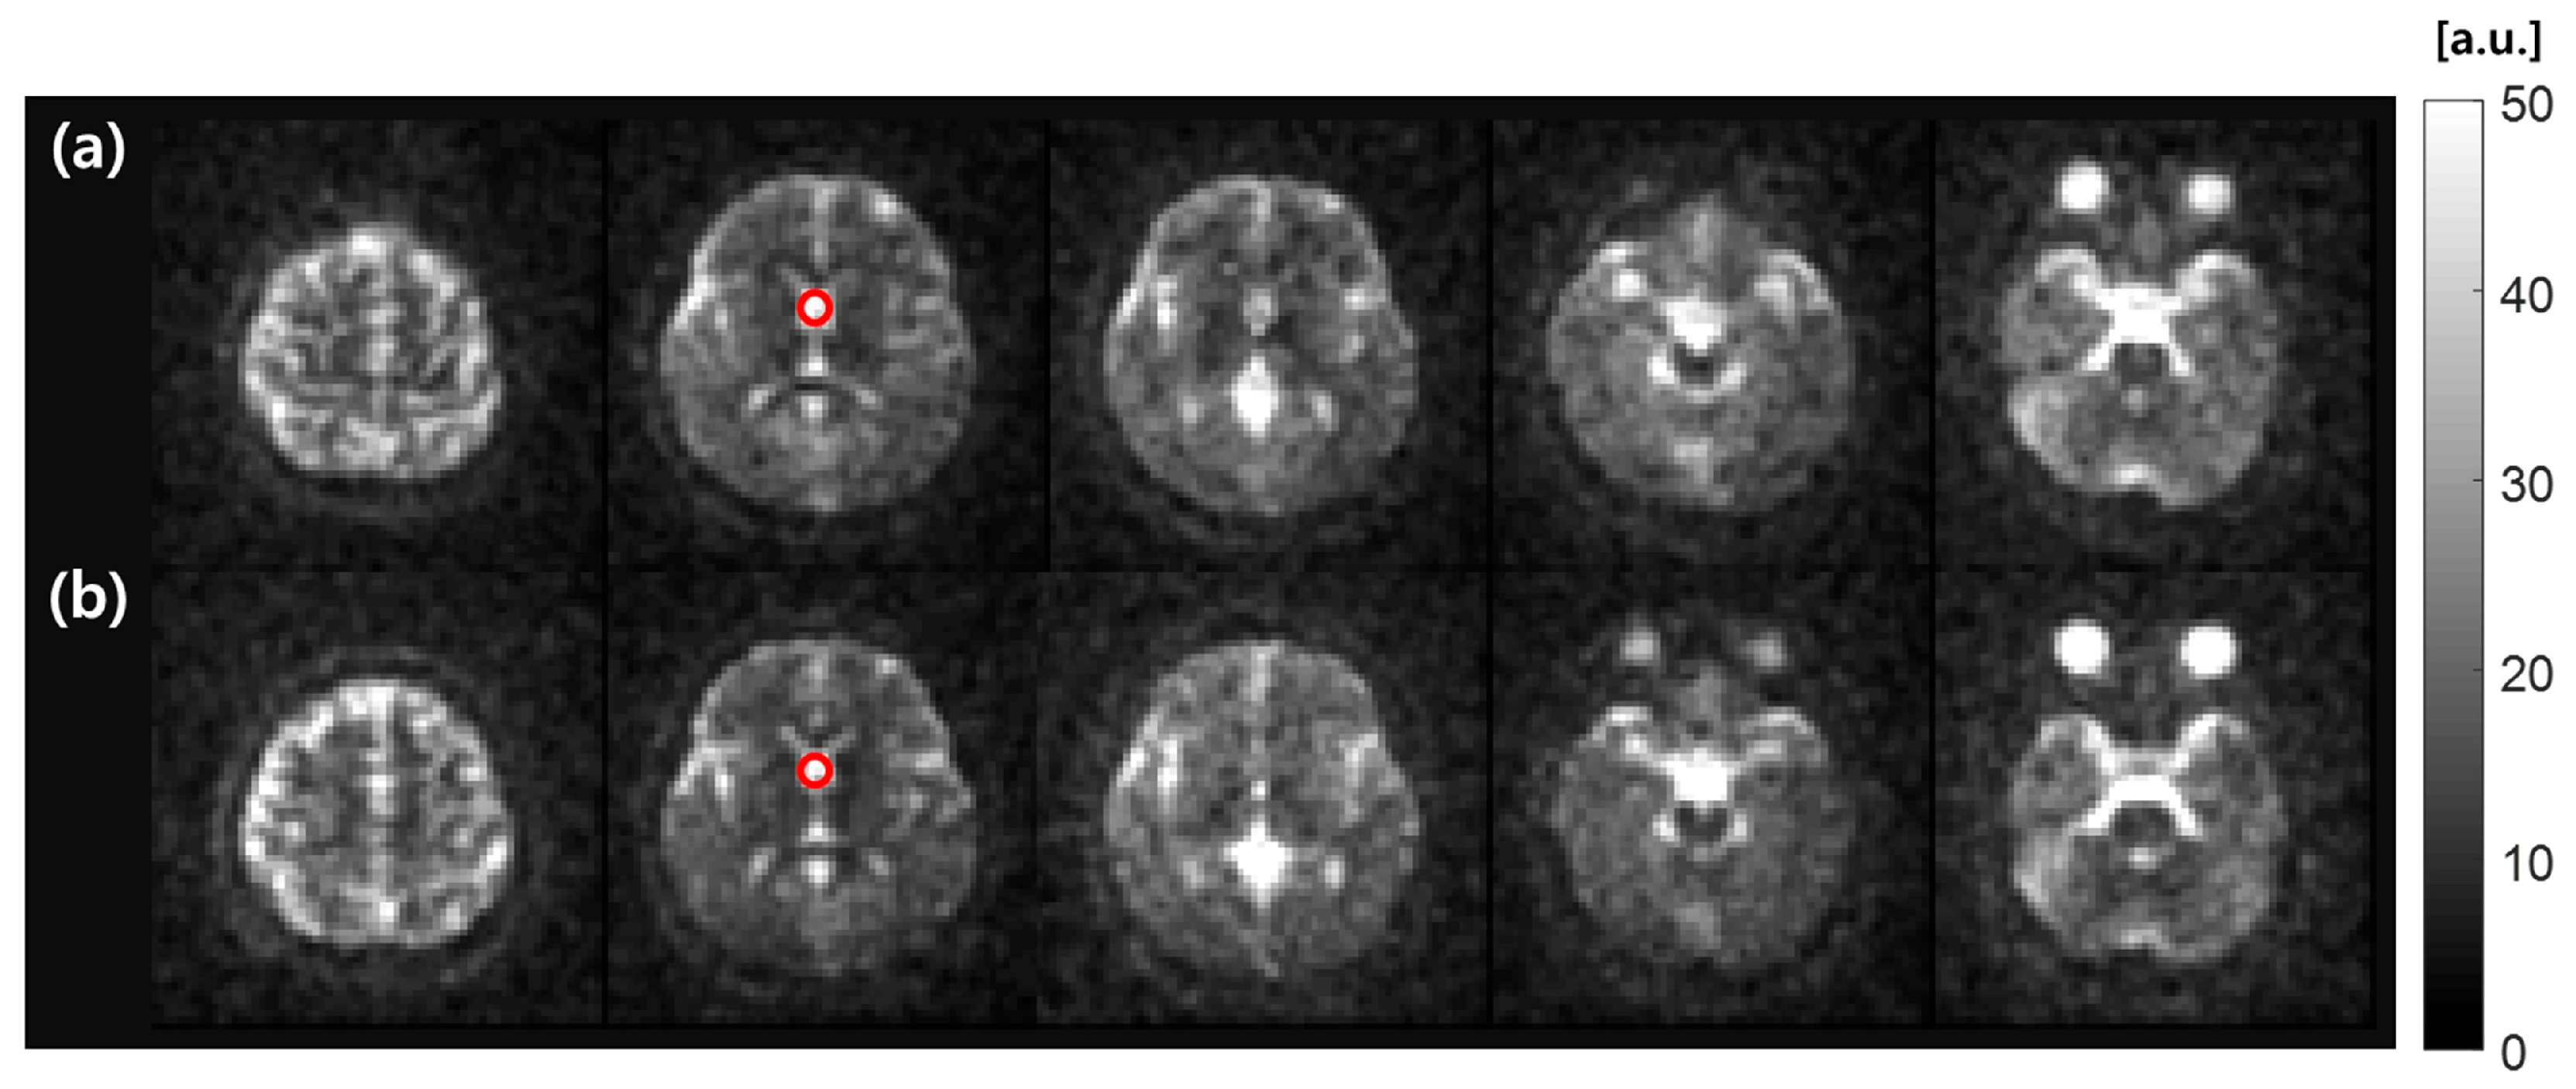

3.3. MR Imaging Experiments

| Sequence | Dual-TR (AFI) | T1-weighted MPRAGE | UTE (DAM) | UTE |

| Nominal FA (°) | 60 | 7 | 45 and 90 | 32 |

| TE/TR (ms) | 3.9/20 and 120 | 2.6/5.5 | 0.19/120 | 0.19/100 |

| FOV (mm3) | 240 × 240 × 240 | 240 × 240 × 240 | 240 × 240 × 240 | 240 × 240 × 240 |

| Acquisition matrix | 120 × 120 | 240 × 240 | - | - |

| Reconstruction matrix | 120 × 120 | 240 × 240 | 68 × 68 | 68 × 68 |

| Image resolution (mm2) | 2 × 2 | 1 × 1 | 3.5 × 3.5 | 3.5 × 3.5 |

| Slice thickness (mm) | 8 | 1 | 8 | 8 |

| Average | 1 | 1 | 1 | 3 |

| Scan time (min) | 2 min 47 s | 6 min 6 s | 6 min 1 s | 30 min |